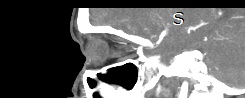

Орбиты (или глазницы) – это костные углубления в лицевом черепе, где расположены глазные яблоки, окруженные жировой клетчаткой, а также слезные железы, слезные каналы, сосуды, нервы, мышцы и связки глаза. Такая небольшая по объему область содержит важные анатомические структуры, обеспечивающие нормальную функцию органа зрения.

Кроме того, область орбиты тесно связана с близлежащими структурами – полостью черепа с расположенным в ней головным мозгом, а также с полостью носа, околоносовыми пазухами и носоглоткой. Различные патологические процессы могут развиваться как в самой глазнице, так и в околоорбитальных структурах, но при этом распространяться на область орбит.

Сложное строение глазницы и взаимосвязь с соседними анатомическими структурами затрудняет диагностику заболеваний глазного яблока и его придатков. Одним из наиболее информативных методов обследования органа зрения и окружающих тканей является мультиспиральная компьютерная томография. Кроме высокой информативности методика отличается быстротой и неинвазивностью (то есть не требует вмешательства в организм человека). Принцип получения изображений построен на применении ионизирующего излучения и разной способности тканей поглощать рентгеновские лучи.

Мультиспиральная компьютерная томография лучше всего визуализирует ткани с высокой плотностью, к которым, в частности, относится костная ткань. Это делает КТ незаменимой при диагностике травматических повреждений глазниц, а также для выявления инородных тел орбит.